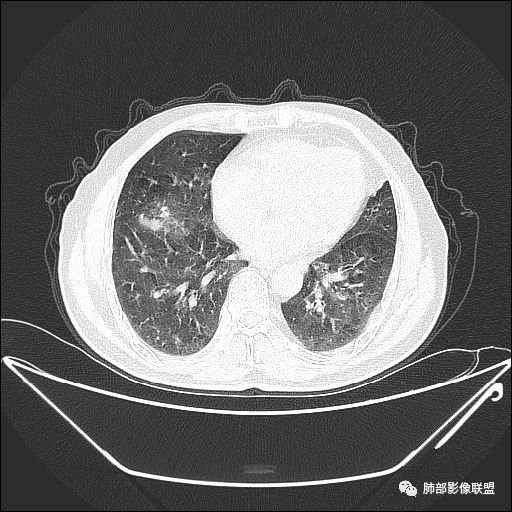

住院4天后行胸部增强CT

动脉期

老年男性,因“咳嗽咳痰1月余。”入院。病程中咳嗽咳痰,咳黄白痰,间断咯少许鲜红色痰血。PPD阳性。胸CT:右肺中叶外侧段支气管管腔阻塞,大片实性病变,病灶边缘光滑,部分边缘膨隆,可见分叶,肺门及纵隔可见肿大淋巴结,并可见钙化。增强可见病灶明显强化,而且延迟强化明显,病灶内多发低密度区,内见血管影,血管变细、部分血管破坏。考虑恶性病变可能性大,鉴别慢性肉芽肿性病变。

胸CT:跨叶大肿块,主体在中叶,右中叶外侧段支气管阻塞,病灶部分边缘膨隆,可见分叶,部分边缘平直,肺门及纵隔可见肿大淋巴结。增强病灶不均匀强化,延迟强化明显,病灶内多发低密度区,内见血管飘浮,部分血管变细、模糊。考虑:恶性病变可能性大,大细胞?淋巴瘤?鉴别慢性肉芽肿性病变。

右肺中叶软组织肿块,外围向内生长,叶间胸膜向前内移位,肿块近肺门侧跨叶,中叶外侧段支气管截断,密度不均匀,双侧肺门及隆突下见肿大淋巴结,增强后呈中度不均质强化,肺动脉供血,多发坏死区,边界尚清,坏死区域内见结构,结合病史考虑恶性,鉴别诊断1结核,爬行征是沿支气管树分布,外宽,内窄,周围有卫星灶,内气管狭窄后扩张,此例沿叶间胸膜长轴分布,气管有截断,不典型。2炎性肉芽肿,符合的地方下方层面增强后延迟性轻度环形强化,不符临床无发热等急性感染病史,实验室指标不符,病灶周围渗出及慢性炎性改变有,不明显。